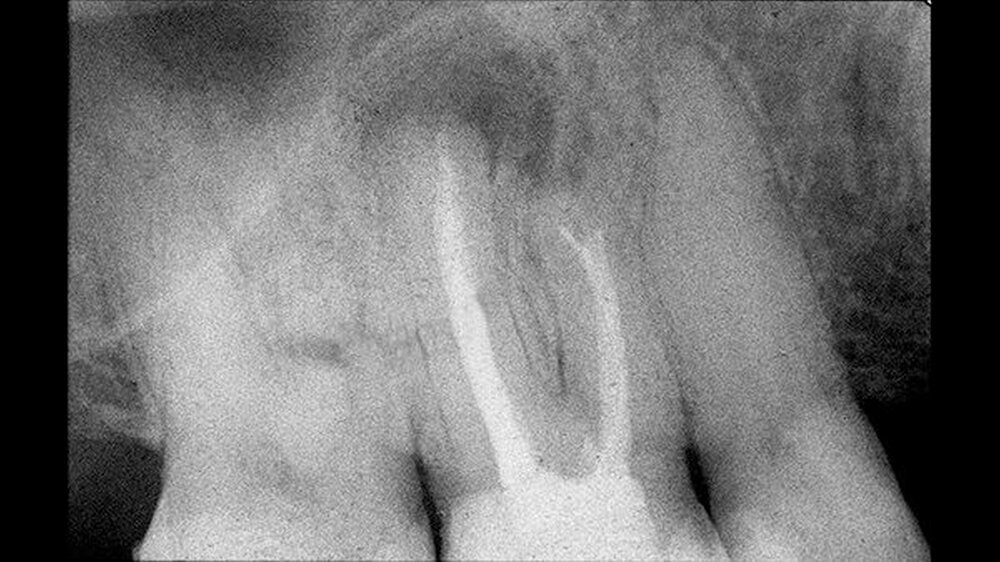

Um die mesiobukkale Wurzel freizulegen, wurde der Knochen darüber entsprechend entfernt (Abbildung 2) und eine Wurzelspitzenresektion an der mesiobukkalen Wurzel Zahn 16 durchgeführt. Das Granulationsgewebe konnte vollständig entfernt werden und wurde für eine histopathologische Untersuchung eingeschickt.